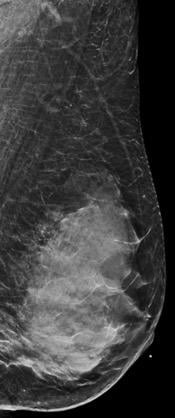

Breast density is divided into four categories, from lowest to highest amounts of fibroglandular tissue composition. Category A: Almost entirely fatty (least amount of fibroglandular tissue). Category B: Scattered fibroglandular tissue. Category C: Heterogeneously dense. Category D: Extremely dense (most amount of fibroglandular tissue).

Breast tissue is composed of a mixture of milk ducts, glands and supportive tissue, which is collectively called fibroglandular tissue and fat. The radiologist who reviews the mammogram analyzes overall breast density, which is the ratio of the amount of fibroglandular tissue to fatty tissue. Women with dense breasts have more fibroglandular tissue than fatty tissue. Fibroglandular tissue appears white on a mammogram and fat appears black. It becomes harder to detect a white cancer against a white background — imagine trying to find a polar bear in a blizzard. Dense tissue is harder to see through to detect abnormal findings. As breast density increases, cancer detection becomes more difficult. Additionally, breast cancer risk rises with increasing breast density. Multiple studies have indicated that there is a two- to six-fold increased risk of breast cancer for a woman who has an extremely dense breast versus a woman with an almost entirely fatty breast.4

Breast density is divided into four categories, from lowest to highest amounts of fibroglandular tissue composition:

Category A: Almost entirely fatty (least amount of fibroglandular tissue)

Category B: Scattered fibroglandular tissue

Category C: Heterogeneously dense

Category D: Extremely dense (most amount of fibroglandular tissue)